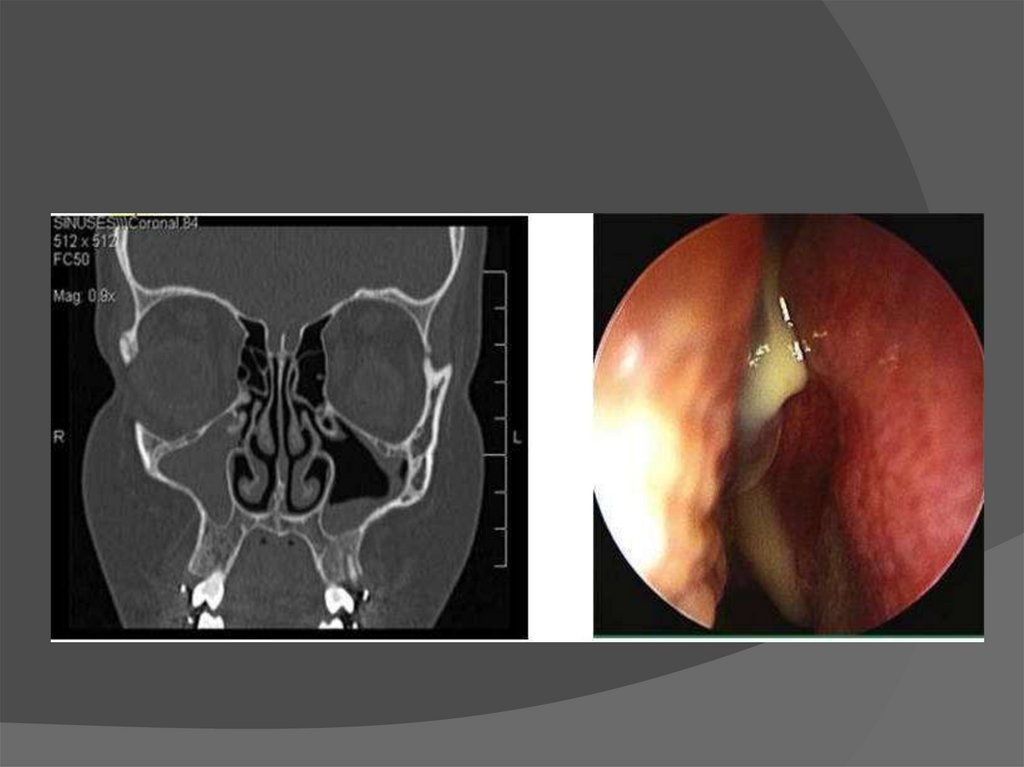

Инородное тело верхнечелюстной пазухи

26. Инородное тело верхнечелюстной пазухи